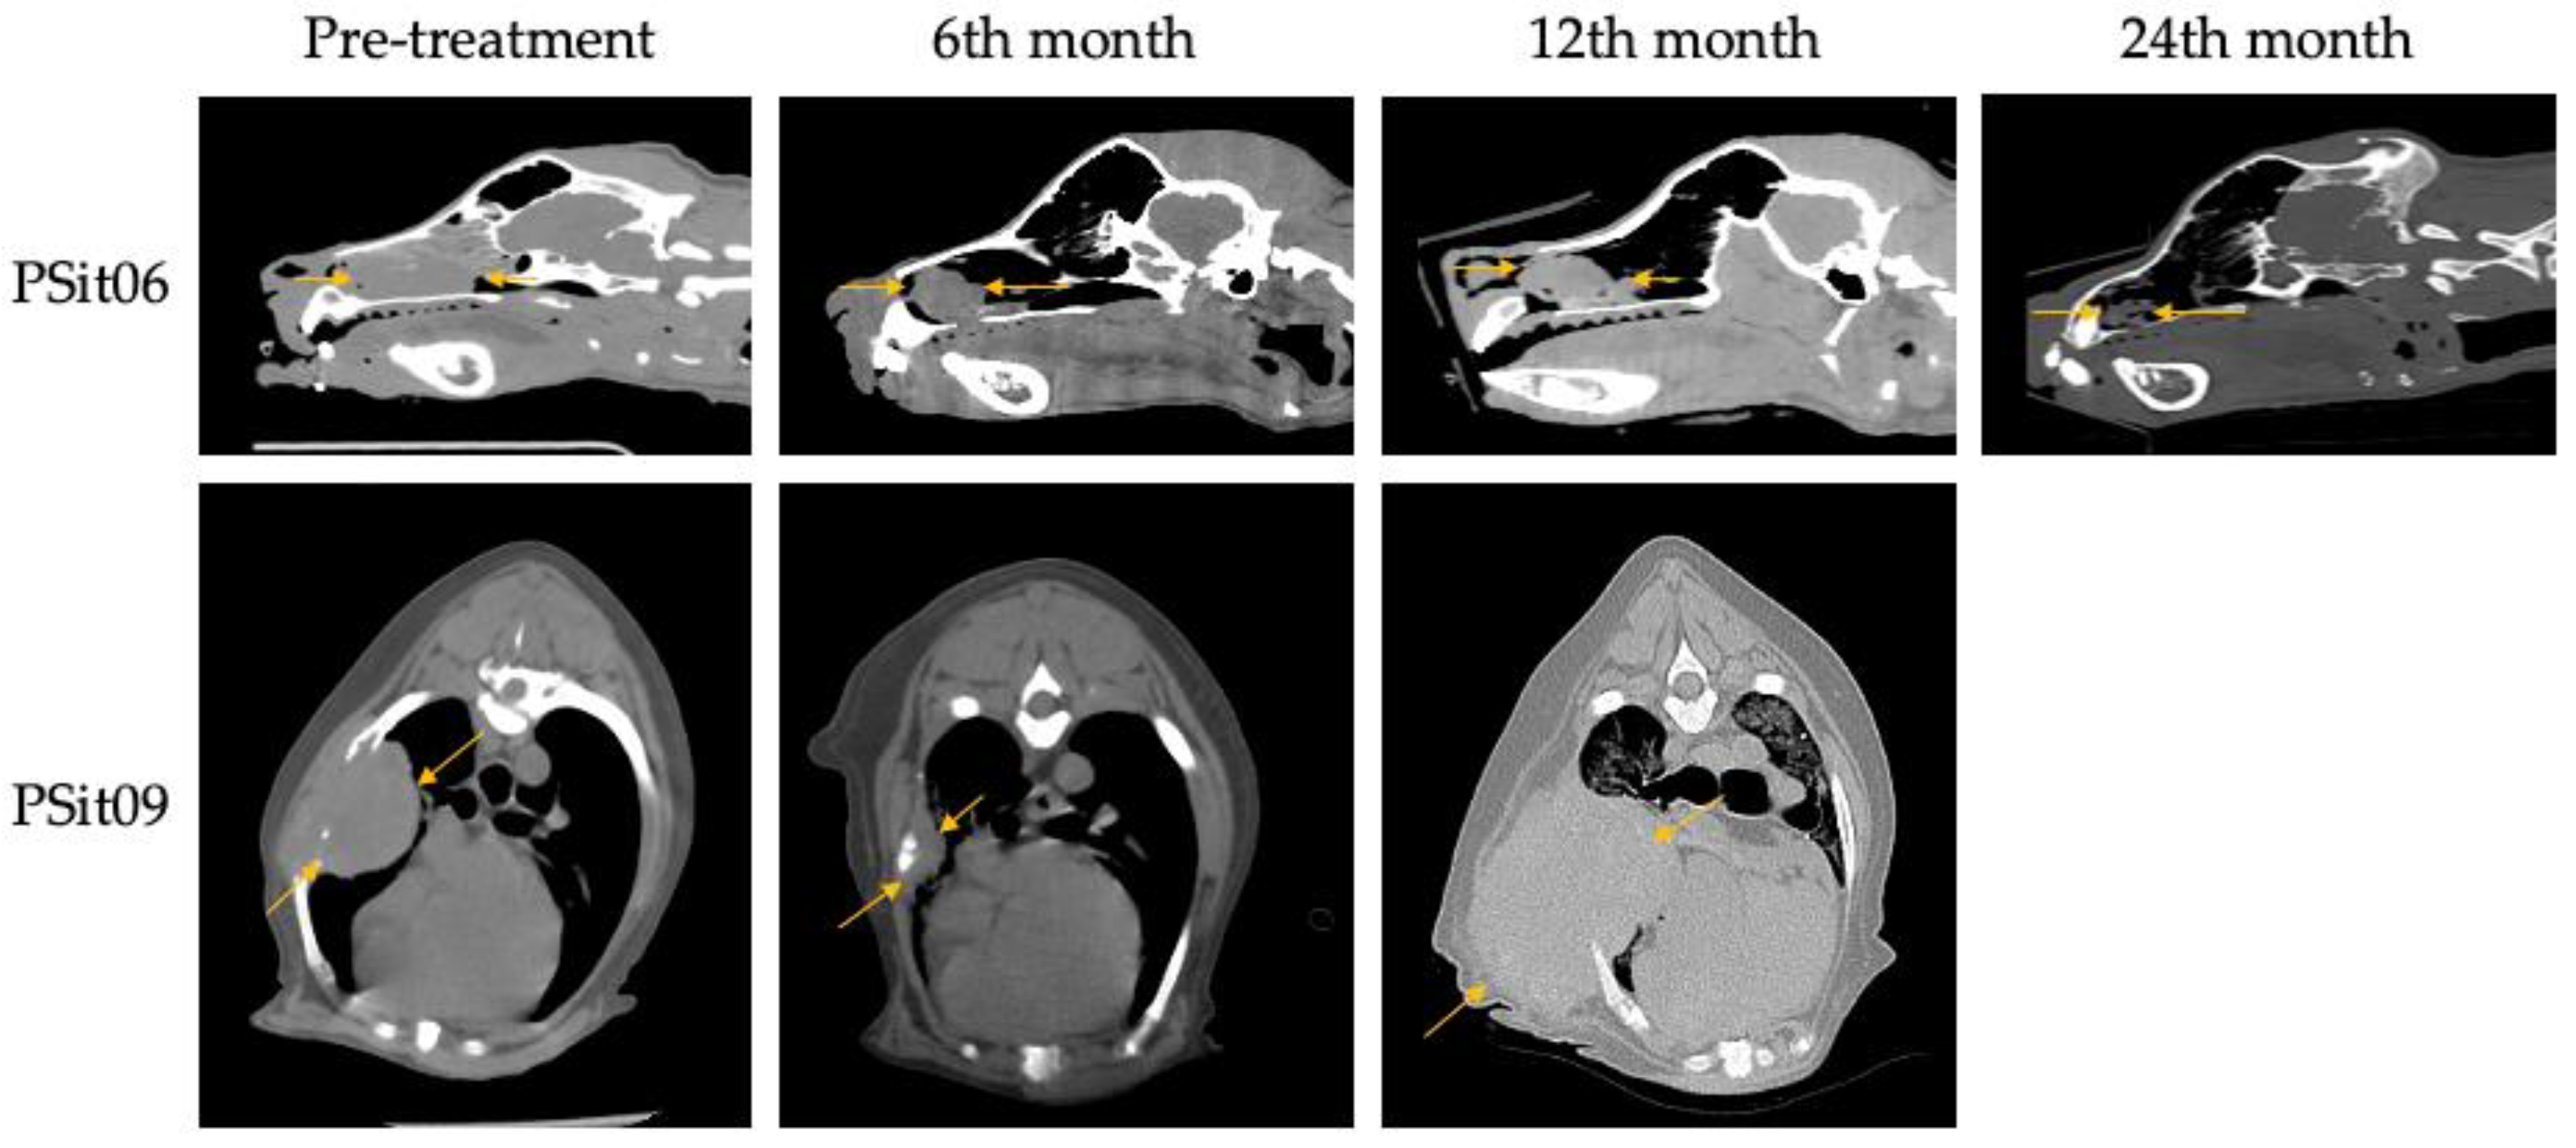

| PSit06 | Mixed | 11 | Male | Nasal Adenocarcinoma | 3 | To date (2 years 7months) |

| PSit09 | Cocker Spaniel | 13 | Female | Squamous Cell Carcinoma (rib wall) | 2 | 389 |